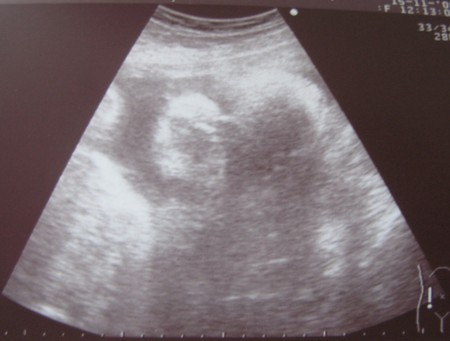

А вот его первая фотка, тут его личико: (может кому-то не совсем понятно будет, ближе виднее)

Срок поставили 32-33 недели. А ПДР 6-7 января )))